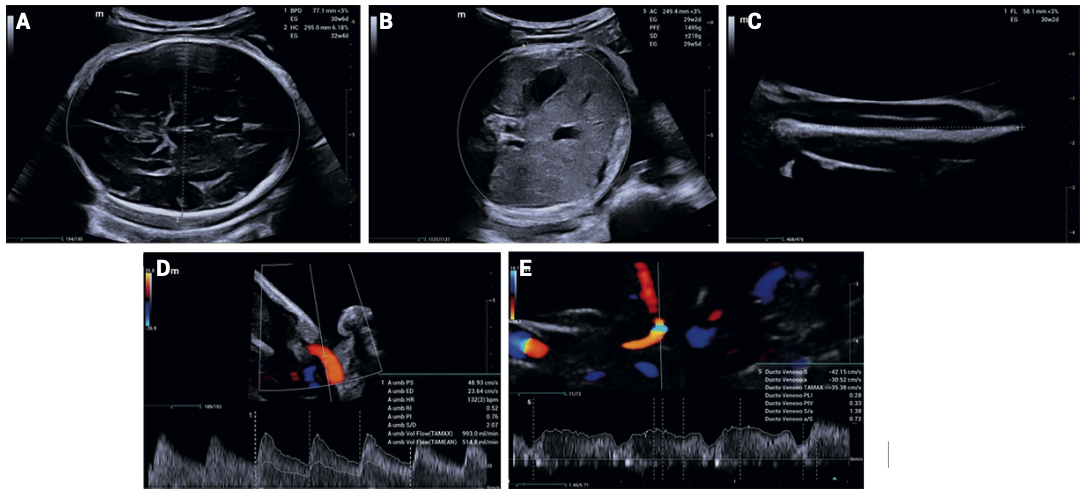

Por lo que se refiere a las condiciones del feto, se estableció el diagnóstico de restricción del crecimiento fetal temprano, estadio I. De acuerdo con la primera ecografía se documentó la existencia de un feto único vivo en presentación cefálica, con fetometría promedio correspondiente a 29 semanas, peso estimado de 1371 gramos (percentil < 3), hemodinamia fetal conservada (Figura 4), volumen del líquido amniótico de 4.1 cm por máxima columna vertical, placenta corporal anterior grado I y longitud cervical de 27 mm. A partir de entonces permaneció en vigilancia mediante ultrasonido de crecimiento y evaluación hemodinámica semanal.

<strong>Figura 4</strong>

Figura 4. Evaluación ecográfica de crecimiento y hemodinamia fetal. A. Corte axial, cefálico, que muestra el diámetro biparietal y la circunferencia cefálica por debajo del percentil 3 para las semanas de gestación. B. Corte axial, abdominal, circunferencia abdominal disminuida, sugerente de restricción del crecimiento fetal. C. Medición de la longitud femoral igualmente por debajo de percentil 3. D. Doppler de la arteria umbilical con índice de pulsatilidad y resistencia en límites normales. E. Doppler del ductus venoso con onda a positiva y patrón trifásico normal, consistente con hemodinamia fetal conservada.

En la última ecografía, a las 36 semanas de gestación, se encontró en presentación pélvica, frecuencia cardiaca de 143 lpm, con fetometría promedio correspondiente a 30.1 semanas, con peso fetal estimado de 1579 g (percentil < 3). El índice de líquido amniótico se determinó en 17.0 cm, placenta corporal anterior, hemodinamia fetal conservada y perfil biofísico 8/8. Con base en estos hallazgos se confirmó la persistencia del diagnóstico de restricción del crecimiento fetal estadio I.